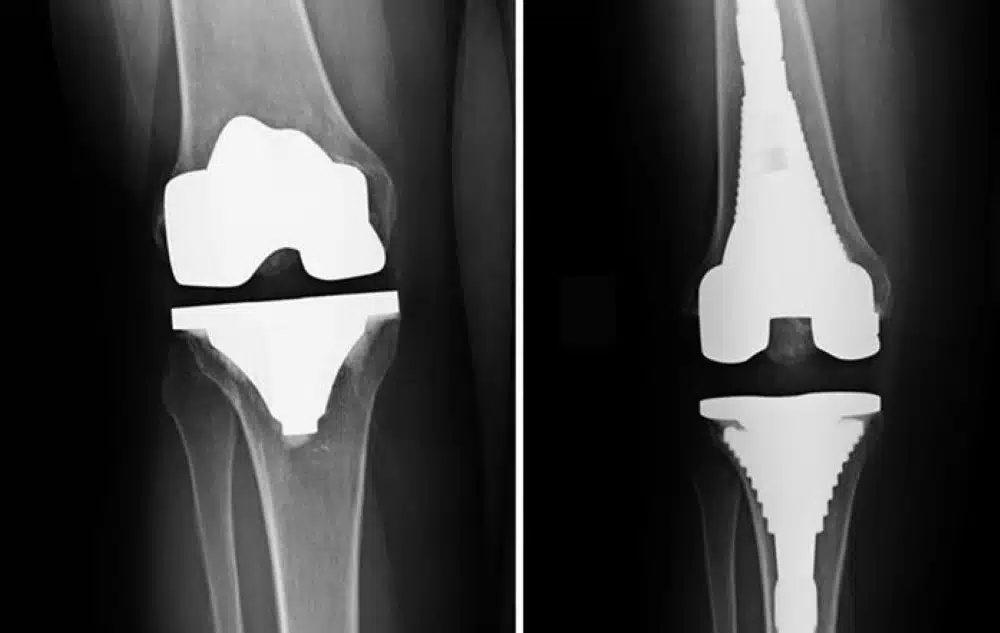

At the beginning of the surgery, an incision about 15 to 25 centimeters long will be made on the joint position of the knee, providing enough space for the surgeon to reach kneecaps and cutaway surfaces of damaged joints. During the total knee arthroplasty, damaged bones of knee joints are cut away and cartilage from thighbones, knee cap, and shinbone. The second step during this surgery is to replace the damaged parts with a prosthesis, which is an artificial joint made of polymers, metal alloys, or plastic. Type of prosthesis and surgical techniques are chosen by surgeons based on different factors, such as weight, knee size, and shape, overall health condition of the patient, his or her age, and activity level. A typical total knee arthroplasty will take about two hours. This time can be prolonged in the case of unpredicted complications during the surgery.

Knee replacement surgery step by step:

- The surgeon starts the operation by a small cut in front of your knee to get access the patella bone.

- The patella bone will be removed from the knee joint.

- When your knee joint expose directly, the bones diameter and length will be measured by your surgeon and a proper and exact cut will be made in the bones.

- The metal part of implant attach to the distal part of femoral bone. The attachment graft by bone powder.

- The lower part of the implant attaches to tibia bone of the leg and fixed by bone powder.

- Before putting the patella bone on the knee joint, the surgeon may sleek the patella bone and repair the joint by a plastic material to fix and coordinate the total knee joint.

- Finally, the surgeon will flex and extend your knee joint to check accurate function of the knee.

Total knee articulation surgery or TKR:

- In total knee arthroplasty surgery, both sides of the knee joint cartilages are removed. This process is quite common. The surgery takes about 1 to 3 hours and then the pain is lessened, but the scar tissue around the surgical site may prevent the patient from bending or moving easily.

Partial replacement of knee joint or PKR :

This type of replacement occurs only on one side of the knee joint. Fewer bones and cartilages are removed and therefore less surgical incision and shorter duration than total dislocation surgery.